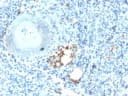

- Description: It recognizes a protein of 35kDa, which is identified as tartrate-resistant acid phosphatase (TRAcP). It exists as two isoforms (5a and 5b). This MAb reacts with both the isoforms. Serum TRAcP 5a is secreted by macrophages and dendritic cells and increased in many patients of rheumatoid arthritis. Serum TRAcP 5b is produced from osteoclasts and elevated during bone resorption. TRAcP is an iron containing glycoprotein, which catalyzes the conversion of orthophosphoric monoester to alcohol and orthophosphate. It is the most basic of the acid phosphatases and is the only form not inhibited by L(+)-tartrate. TRAcP is synthesized as a latent proenzyme and is activated by proteolytic cleavage and reduction. Normally, TRAcP is highly expressed by osteoclasts, activated macrophages, neurons and endometrium during pregnancy. Expression of TRAcP is increased in certain pathological conditions such as Leukemic Reticuloendotheliosis (Hairy Cell Leukemia), Gaucher’s Disease, HIV-induced Encephalopathy, Osteoclastoma and in osteoporosis and metabolic bone diseases. Anti-TRAcP antibody labels the cells of Hairy Cell Leukemia (HCL) with a high degree of sensitivity and specificity. Other cells stained with this antibody are tissue macrophages and osteoclasts.

- Applications: IHC-P